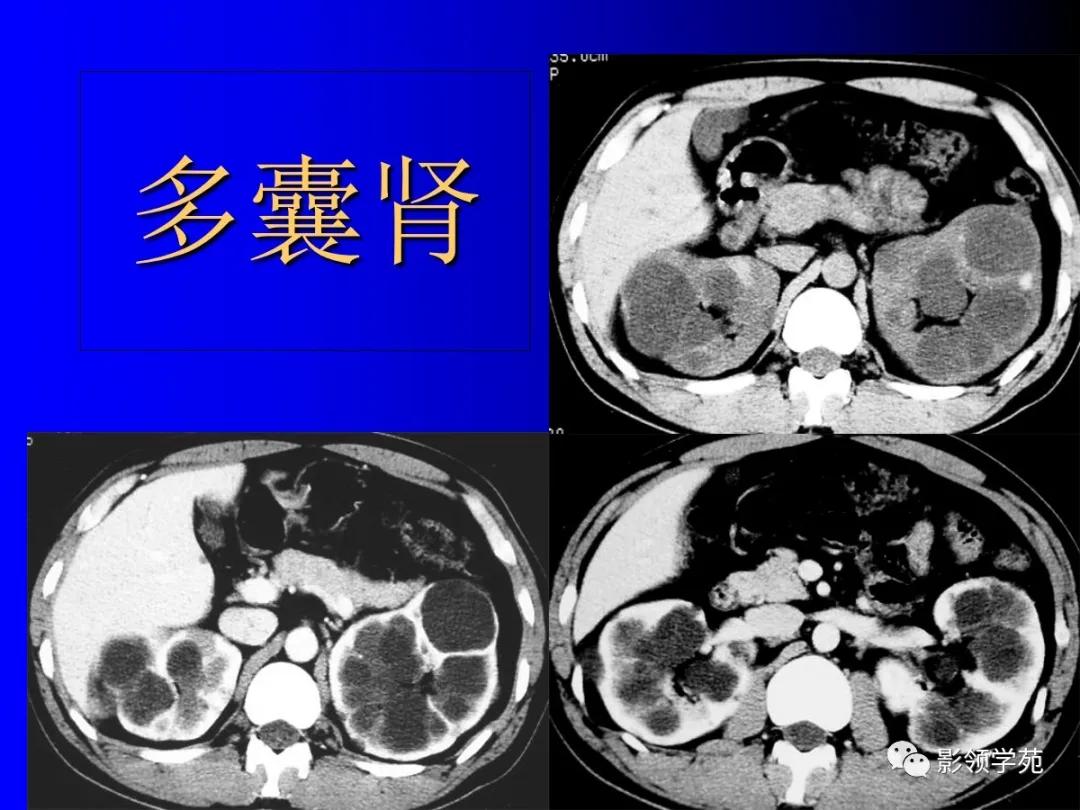

6、常染色体显(隐)性多囊肾

为遗传性肾发育异常。

-

显性者囊肿随年令逐渐增多增大,正常肾组织逐渐减少,患者常在40-50岁左右出现肾功能衰竭。

(隐性者多见于婴幼儿,偶见于青少年,此型常合并先天性肝纤维化,预后差。)